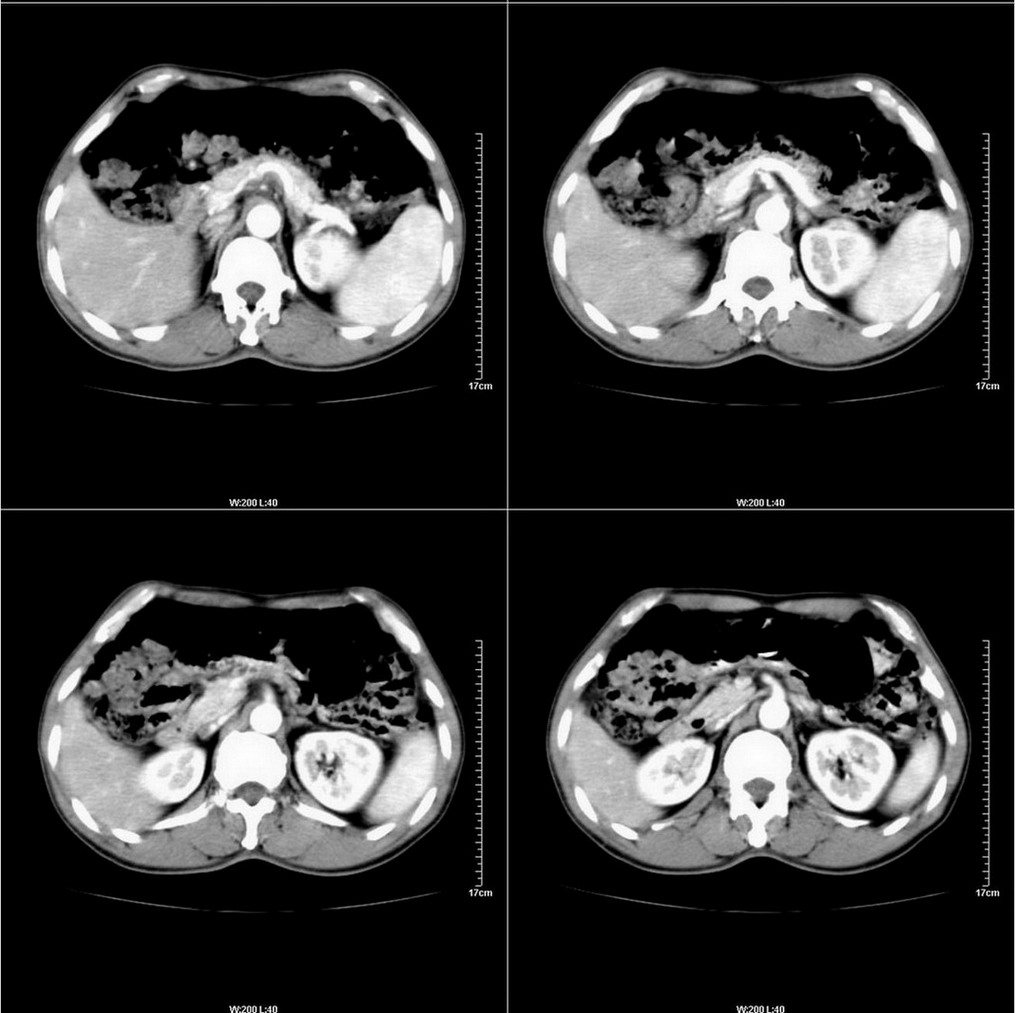

标题: CT14220:男性,59岁。腹部疼痛不适半年余。 [打印本页]

标题: CT14220:男性,59岁。腹部疼痛不适半年余。

肝右叶5段小囊肿。

肝右叶占位(囊肿?小肝癌?).

考虑:1、肝右叶下部小囊肿;

2、胃可能为准备充盈不良所致,必要时请胃镜进一步检查。